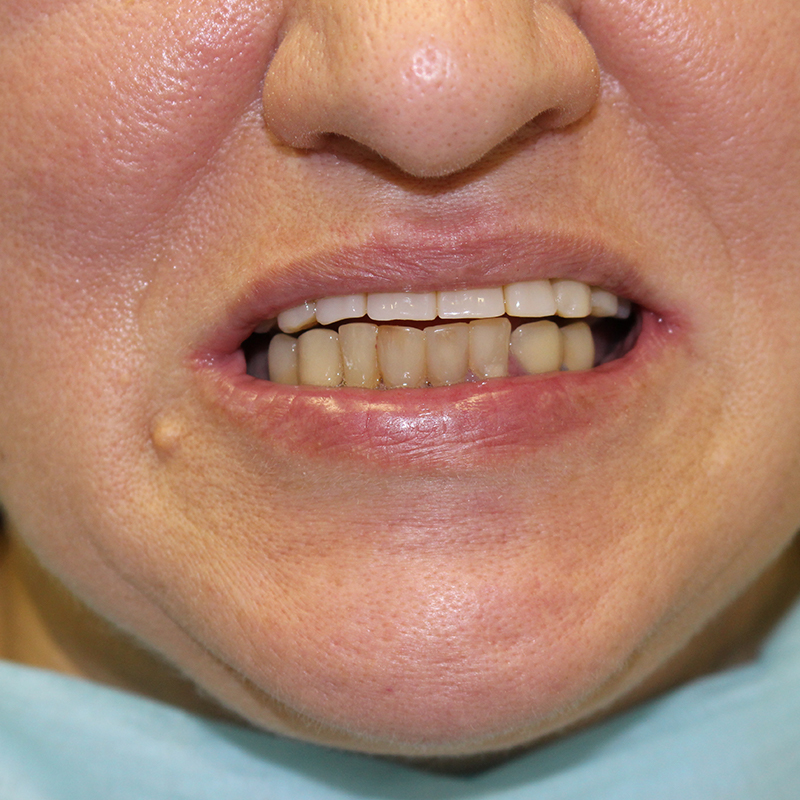

Пациентка обратилась в «Стоматологию Комфорта» с жалобой на отсутствие зубов верхней челюсти. По результатам обследования врач стоматолог-ортопед, хирург-имплантолог Мельников Алексей Владимирович назначил имплантацию по методу «all-on-4». По истечении 6 месяцев после операции проведено обслуживание условно-съёмного протеза. Также врач начал восстановление нижней челюсти коронками в комбинации с бюгельный протезом.

- восстановление нижней челюсти коронками в комбинации с бюгельным протезом.